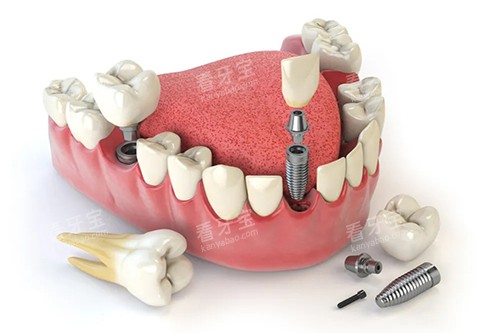

在种植牙方面,北京中诺口腔的医生能够根据患者的具体情况,制定个性化的种植方案。

他们熟练掌握各种种植技术,如即刻种植、小创口种植等,能够有效缩短治疗时间,减少患者的痛苦。

同时,医生们还会在种植过程中严格把控每一个环节,确保种植的成功几率和稳定性。

在种植牙过程中,使用了靠前的种植导航系统。

该系统可以通过计算机模拟种植过程,更好确定种植体的位置和角度,提高种植的比较准性和成功几率。

同时,还配备了激光设备,在种植手术中可以减少出血和创伤,促进伤口愈合。